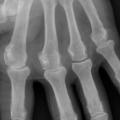

Chondrocalcinose articulaire

ARTHROPATHIES A CRISTAUX

Image